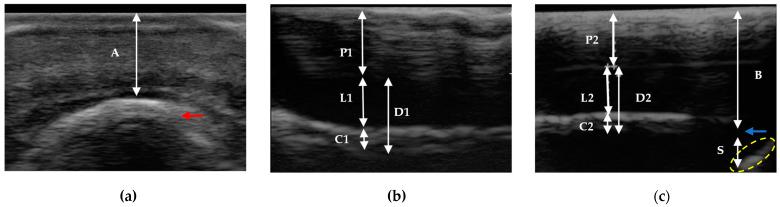

The transmural ultrasound allows for the definition of the normal appearance of the hoof tissues and internal structures. Determining such measurements and proportions could contribute to evaluations of the normal spatial distal phalanx-hoof relationship. The objective was to describe the hoof's dermis and epidermis measurements using the transmural technique, in comparison with DR and anatomical sections. Sixty-two healthy hooves without digital radiographic abnormalities, made up of 30 anatomical pieces (phase 1) and 32 alive horse hooves (phase 2), and 16 sagittal sections of the first ones were used. The proximal and distal planes were compared, defining the following measurements: coronary band-extensor process, distal phalanx apex-hoof wall, sole dermis, middle stratum, parietal dermis, lamellar layer, the sublamellar dermis, and ratios between them. Most of the measurements were consistent among methods. Some showed measurement differences and a minority was impossible to determine. The transmural technique allowed for the observation and replication of measurements of the hoof structures, described with other diagnostic aids. It also allowed for the implementation of new measurements that would help to determine the spatial location of the distal phalanx. Additionally, it contributes to the visualization of normal findings, which will be useful to compare variations in the different phases of laminitis.

摘要

透壁超声可用于确定蹄组织和内部结构的正常外观。确定这些测量值和比例有助于评估远节趾骨与蹄的正常空间关系。目的是使用透壁技术描述蹄真皮和表皮的测量值,并与DR和解剖切片进行比较。使用了62个无数字射线照相异常的健康蹄,其中包括30个解剖标本(第一阶段)和32个活马的蹄(第二阶段),以及其中16个的矢状切片。比较近端和远端平面,定义以下测量值:冠状带-伸肌突、远节趾骨尖-蹄壁、蹄底真皮、中层、壁真皮、板层、板层下真皮以及它们之间的比例。大多数测量值在不同方法之间是一致的。有些显示出测量差异,少数无法确定。透壁技术允许观察和重复蹄结构的测量值,这些测量值可通过其他诊断辅助手段进行描述。它还允许进行有助于确定远节趾骨空间位置的新测量。此外,它有助于可视化正常结果,这将有助于比较蹄叶炎不同阶段的变化。